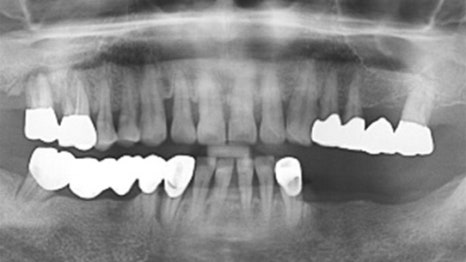

사례 1

과잉진료 없이 꼭 필요한 임플란트만 식립

다른 치과에서 6개 치아 발치 후 12개 임플란트를

권유받았던 환자분이 내원하셨습니다.

연세고운미소치과에서는 레이저 치주 치료를

진행하여 치아를 살리고, 최종적으로 6개의

임플란트만 식립하여 치료를 마무리했습니다.